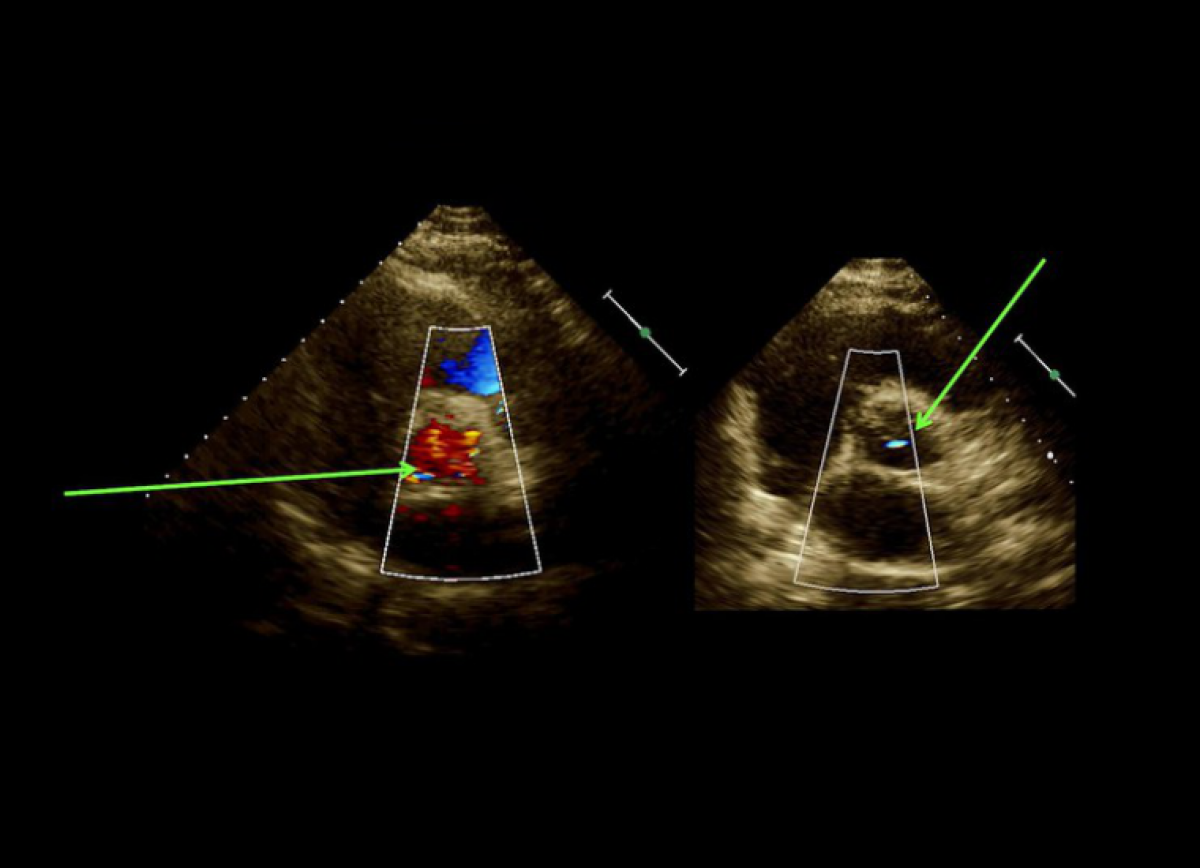

Pacjentka z dusznością spoczynkową, po wymianie zastawki mitralnej.

Dysfunkcja (zakrzepica) mechanicznej zastawki mitralnej.

Echokardiografia przezklatkowa i przezprzełykowa.

Echokardiografia trójwymiarowa.

Ocena sztucznej zastawki mitralnej.